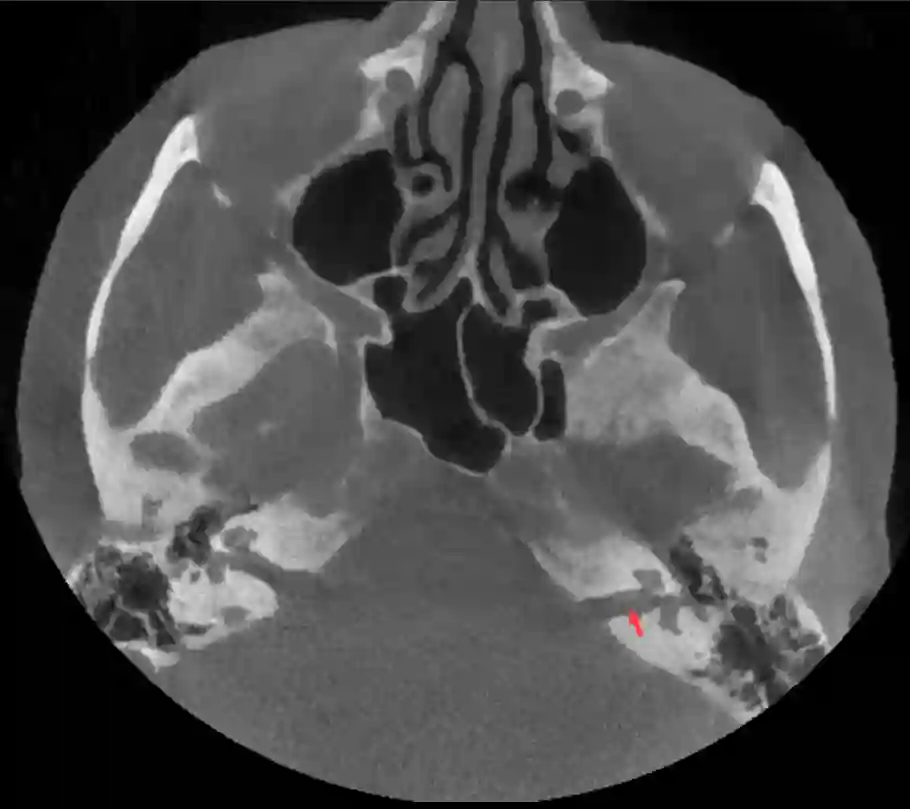

Meatus actusticus internus im CT

Darstellung des Meatus acusticus internus (roter Pfeil) in einem axialen CT Bild.